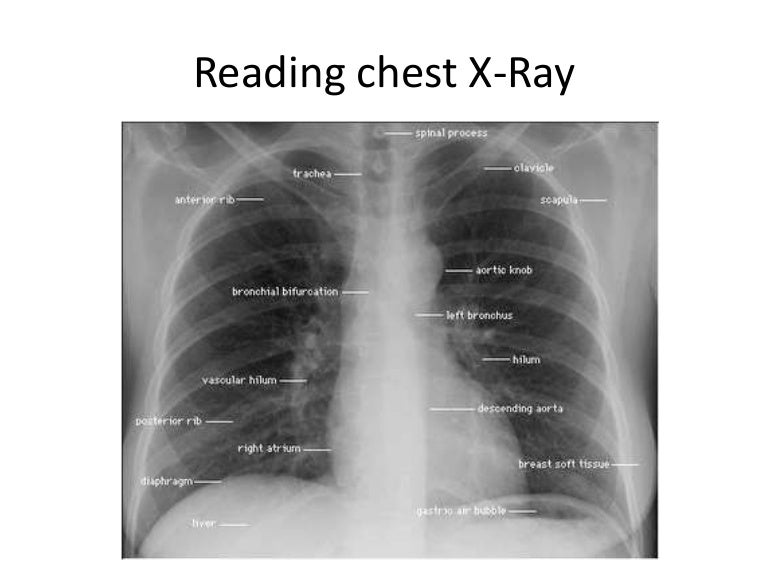

Lung Cancer Screening X Ray

Experience the clarity of Lung Cancer Screening X Ray with our curated collection of comprehensive galleries of images. featuring understated examples of photography, images, and pictures. designed to emphasize clarity and focus. Discover high-resolution Lung Cancer Screening X Ray images optimized for various applications. Suitable for various applications including web design, social media, personal projects, and digital content creation All Lung Cancer Screening X Ray images are available in high resolution with professional-grade quality, optimized for both digital and print applications, and include comprehensive metadata for easy organization and usage. Our Lung Cancer Screening X Ray gallery offers diverse visual resources to bring your ideas to life. Comprehensive tagging systems facilitate quick discovery of relevant Lung Cancer Screening X Ray content. Multiple resolution options ensure optimal performance across different platforms and applications. Time-saving browsing features help users locate ideal Lung Cancer Screening X Ray images quickly. The Lung Cancer Screening X Ray archive serves professionals, educators, and creatives across diverse industries. Instant download capabilities enable immediate access to chosen Lung Cancer Screening X Ray images. Whether for commercial projects or personal use, our Lung Cancer Screening X Ray collection delivers consistent excellence. Professional licensing options accommodate both commercial and educational usage requirements.